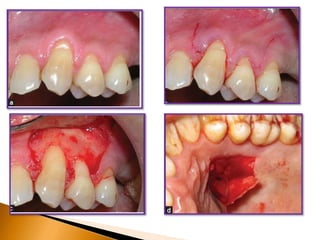

recession - Laterally positioned pedicle graft4

The best-known technique among pedicle grafts is the laterally positioned

pedicle graft introduced by Grupe and Warren and later modified by Grupe.

The success rate of this root coverage procedure was found to be in the

range of 69% ~ 72%.

In this procedure, the adjacent keratinized gingiva is positioned laterally,

and the exposed root surface in the localized gingival recession is

covered.

Guinard and Caffesse reported an average of 1mm postoperative gingival

recession on the adjacent donor site.

The main advantages of the laterally positioned pedicle graft are that it is

relatively easy and not time-consuming, it produces excellent esthetic

results, and a second surgical site is not mandatory.

To reduce the risk for recession on the donor tooth, Grupe suggested that

the marginal soft tissue should not be included in the flap.